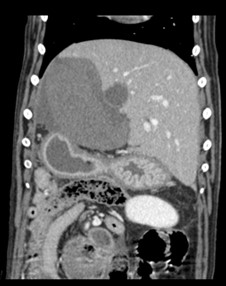

A CT scan revealed Riley was suffering from two liver lobe torsions (LLT), an extremely rare complaint in animals and especially in dogs.

“Riley was stabilised with the help of our anaesthesia team and underwent a CT scan. We the assistance of our imager on duty, we diagnosed Riley with torsion of two of his liver lobes.